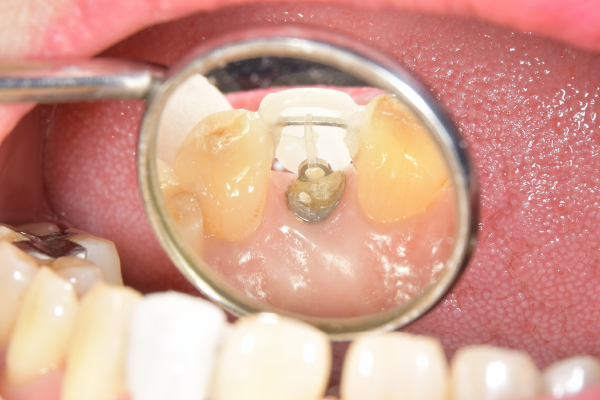

カリエスを取り除くと、遠心の歯質が歯肉縁下になりました。

カリエスが大きく、舌側では歯肉より上に残存歯質がなくなってしまっている。このままではコア、クラウンの接着ができないため、歯を歯肉より上にだすことが重要です。

右の写真では歯肉の上に歯が一周のこり、その上にコアが入っているのがわかります。